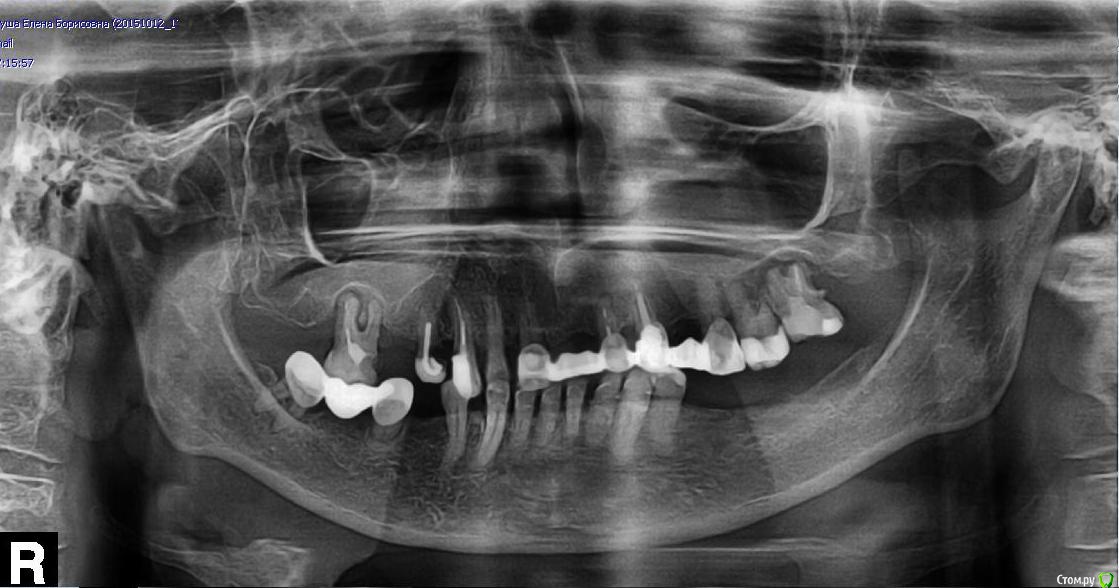

Swa Опубликовано 13 октября, 2015 Поделиться Опубликовано 13 октября, 2015 Здравствуйте, уважаемые специалисты! Пожалуйста, помогите разобраться с возникшей проблемой. Проблема у моей мамы (возраст 67 лет). Я понимаю, что консультирование через третьих лиц не приветствуется, но мама не дружит с интернетом и плохо представляет, что означает «форум» в интернете. Ниже прикрепляю её панорамный снимок (на всякий случай двумя способами, увеличиваются кликом). Где-то месяц назад начала появляться припухлость левой щеки (на снимке справа – зеркальное отражение). В данный момент припухлость довольно ярко выражена, кожа натянута. Лицо стало ассиметричным. Область припухлости: чуть ниже периорбитальной области и спускается вниз вдоль носогубной складки, в непосредственной близости с носом. То есть припухлость находится скорее над передними зубами, а не над боковыми зубами. Покраснения кожи нет.Если смотреть на снимок на мониторе, то проблемная область справа вверху, а не слева.Размеры припухлости примерно: 4,5 см. на 5 см. Боли, по словам мамы, «нет никакой абсолютно». Температура не повышена (36,2 ). Дней 5 назад она ездила в государственную стоматологическую поликлинику, её долго осматривали терапевт, затем несколько хирургов. Простукивали все зубы. Реакции в виде боли не было. Было только «неприятное ощущение» при простукивании верхней «семёрки» с левой стороны (на снимке справа).Все (и терапевт, и хирурги) единогласно сказали, что припухлость данной локализации могут давать только передние зубы, а с ними, якобы, всё в порядке (судя по реакции на простукивание).Сказали также, что, возможно, это какое-то заболевание челюсти и что они могут выписать направление в стационар челюстно-лицевого отделения. Два дня спустя она сделала панорамный снимок (в поликлинике направить на рентген не посчитали нужным). Также я увидела на верхней челюсти над третьим и четвёртым зубом (на снимке справа вверху) сильное воспаление десны (больше над третьим). Десна ярко розового цвета, выступает (десна) немного вперёд, но без свища! По словам мамы, такое воспаление десны возникло почти сразу после установления моста с коронками. Мост вверху установлен около трёх лет назад. Я понимаю, что, возможно, нужно обратиться также к дерматологу, но прежде чем это сделать, хотелось бы исключить проблему с зубами / челюстью. Была бы очень признательна за подсказки коллективного разума: 1) Видите ли Вы на снимке какое-либо заболевание челюсти, требующее госпитализации в стационар челюстно-лицевой хирургии? Возможно, остеомиелит (или что-то ещё)? Или по панорамному снимку подобные заболевания определить невозможно?2) Есть ли воспаление вокруг корней третьего и четвёртого зубов (на снимке справа вверху)? Повторюсь, над ними очень воспалена десна. Могут ли эти зубы (или воспалённая десна над ними) вызывать ярко выраженную припухлость на щеке?3) Есть ли воспаление вокруг корней верхней семёрки (на снимке справа)? При простукивании неприятные ощущения (+ он немного шатается).4) На какие ещё зубы (судя по снимку) нужно обратить внимание?5) Какие именно зубы (из проблемных на снимке) могут давать такую припухлость (если вообще могут)?6) Какие зубы (из проблемных на снимке) не подлежат лечению и которые необходимо только удалить?7) Какие зубы можно попробовать пролечить?8) Может ли пародонтоз (пародонтит?) (вижу по снимку, что он есть) вызвать такое вот воспаление в виде припухлости на щеке? Заранее большое спасибо всем за ответы, с ув., Светлана. http://s017.radikal.ru/i436/1510/f0/61e1f7d9beaf.jpg Ссылка на комментарий

kozloff Опубликовано 14 октября, 2015 Поделиться Опубликовано 14 октября, 2015 (изменено) Видится мне приличных размеров киста на зубе 11 (первый резец справа вверху)Помимо этого: воспаления на корнях 13 (клык слева), 17 (второй моляр слева), 16 (моляр справа)Так же с Ваших слов подразумевается гигнивит (пародонтит) от мостовидного протеза. Зубы лечению не подлежат.Показания для изготовления полного съёмного протеза.Ситуация сложная, ищите врача, все нужно решать индивидуально, учитывая возраст, самочувствие и настрой пациента. Изменено 14 октября, 2015 пользователем kozloff 1 Ссылка на комментарий

shishok Опубликовано 14 октября, 2015 Поделиться Опубликовано 14 октября, 2015 13-это клык справа,моляр слева-это 27.Я бы ещё посоветовала убрать 14(предпоследний вверху справа(собранный на штифте из проволоки)-он разрушен под пломбой. 1 Ссылка на комментарий